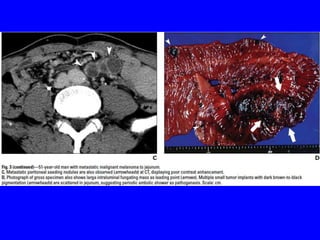

• Metastatic gastric &duodenal melanomas classically appear as small

submucosal nodules that may have central ulceration well-known

“target or bull’s-eye lesions” on endoscopy.

• These lesions may be either pigmented or amelanotic.

• The SI involvement with metastatic tumors is more common in

melanoma than upper or lower GIT due to its rich blood supply&

appear as intraluminal masses or serosal implants, usually

diagnosed on imaging studies.